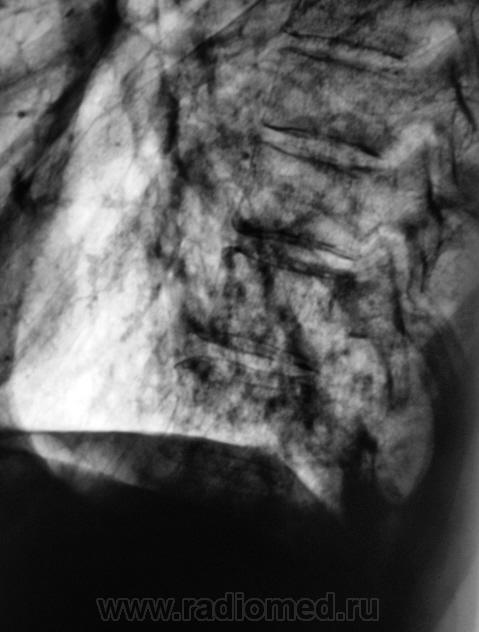

Пациент направлен на рентгенографию ОГК с диагнозом - "Левостороняя пневмония".

Анамнез стандартный. Ранее неоднократно страдал обострениями хронического бронхита. Сейчас вот не нашутку занемог - температура до 38, откашливает мокроту, кашель продуктивный.

Диагноз левосторонней нижнедолевой С10, С9 сементарной пневмонии наверное будет верным, а с учётом фона- с наличием бронхоэктазов.